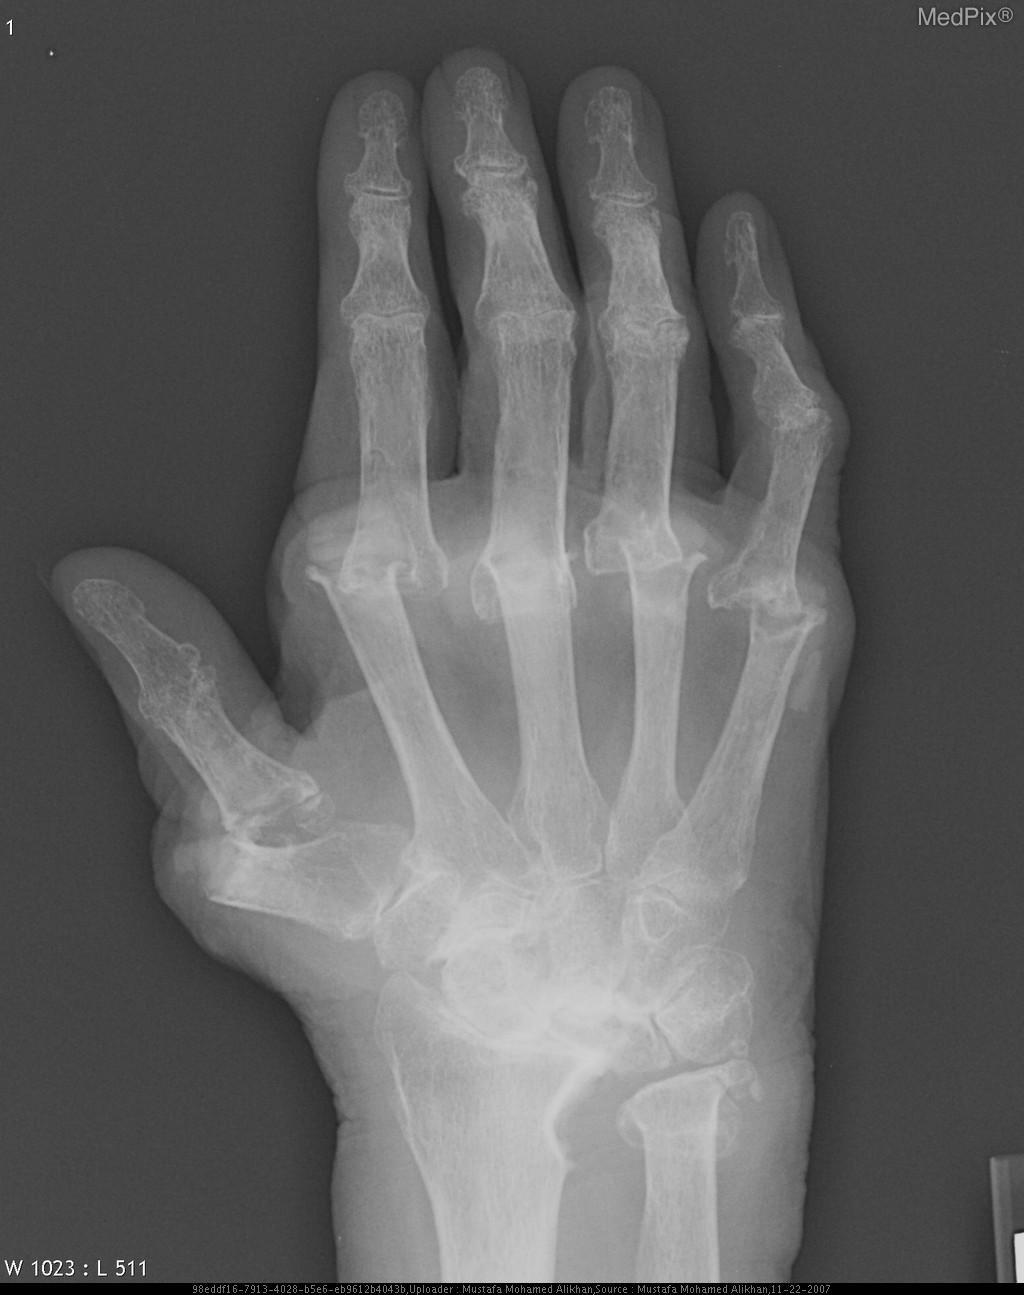

Treatment

06/22/2020

EULAR updated its recommendations for treating rheumatoid arthritis with different therapeutic agents. Do you agree with its recommendation about initiating therapy for patients with RA?